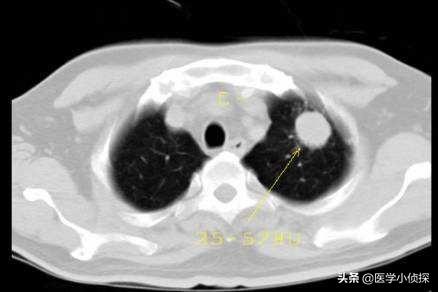

第一个,低剂量螺旋CT!用胸部CT去替代你平时体检拍的胸片来进行肺部的检查,只有这种胸部CT扫描片,才可以早期发现早期肺癌。但是一般情况下,用这个CT发现的早期肺癌,都是长在肺叶里面的周围性肺癌,而针对中心性肺癌,诊断率还是比较低的!因此就下面第二个检查!